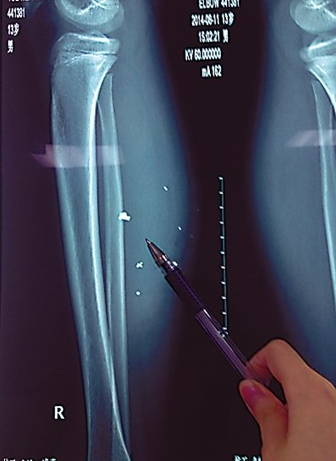

10多塊爆炸物進(jìn)入小腿

第二天,傷勢(shì)過重的平平轉(zhuǎn)院至兒童醫(yī)院,骨科醫(yī)生周悅航說,經(jīng)檢查,平平右小腿腫脹明顯,發(fā)現(xiàn)有爆炸傷伴異物殘留,后側(cè)可見兩處1厘米裂口,傷口較深,約1.5-2厘米。通過X光片可見患兒右小腿皮下多處高密度影,即手機(jī)爆炸后進(jìn)入小腿的異物,大約10處,需通過手術(shù)取出。

由于進(jìn)入皮下的異物較多,平平需要多次手術(shù)。但醫(yī)生們最擔(dān)心的,是手機(jī)爆炸后金屬物進(jìn)入體內(nèi)可能會(huì)對(duì)肌肉造成損傷。今天上午,平平將接受小腿爆炸傷清創(chuàng),并取出部分異物。